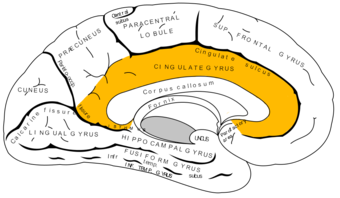

القشرة الحزامية cingulate cortex، تعرف أيضاً بالقشرة الحوفية، هي جزء من المخ يقع في الجانب الإنسي من القشرة المخية. القشرة الحزامية تشمل التلفيف الحزامي بأكمله، والذي يقع فوق الجسم السفني مباشرة، ويستمر حتى التلم الحزامي. القشرة الحزامية عادة ما تعتبر جزءاً من الفص الحوفي.

تستقبل القشرة المخية الإشارات العصبية من المهاد والقشرة الجديدة، وترسلها إلى القشرة الشمية الداخلية عن طريق الحزام. وهي تعتبر جزءاً مدمجاً في الجهاز الحوفي، المسئول عن تشكيل ومعالجة المشاعر،[1] التعلم،[2] والذاكرة.[3][4] الجمع بين هذه الوظائف الثلاثة يجعل للقشرة الحزامية تأثير كبير في ربط المخرجات السلوكية بالمشاعر (على سبيل المثال، إجراء ما يتطلب استجابة عاطفية إيجابية، والذي يظهر أثره في التعلم).[5] هذا الدور يجعل القشرة الحزامية بالغة الأهمية في بعض الاضطرابات مثل الإكتئاب[6] وإنفصام الشخصية.[7] ويلعب أيضاً دوراً في الوظائف التنفيذية والتحكم في التنفس.